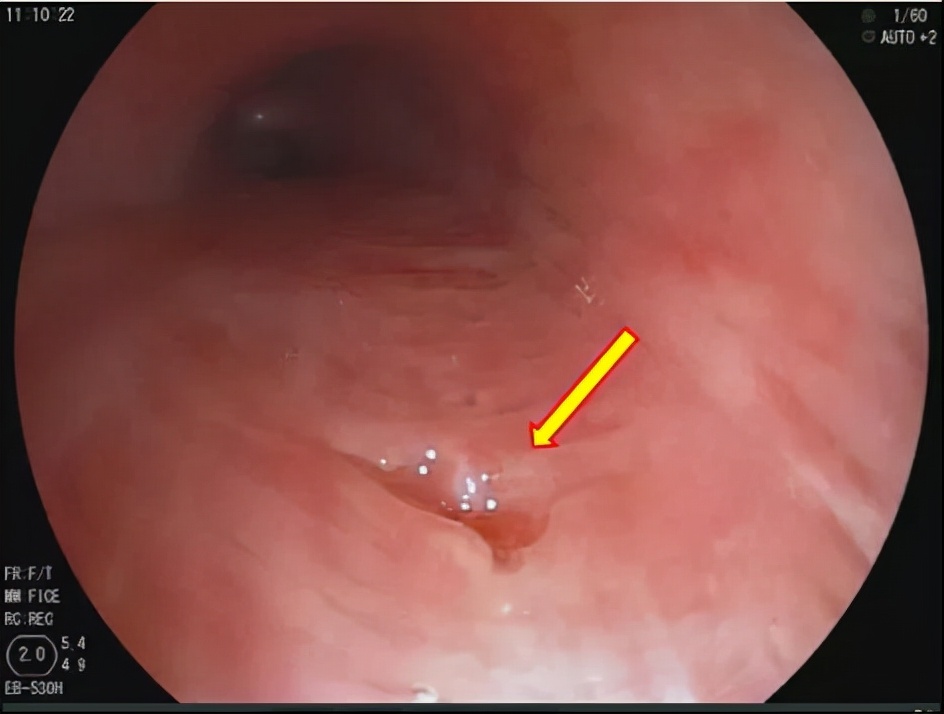

检查当中,医生发现了个大新闻:大梅的左主支气管有一个破口,轻轻按压,还会有分泌物及气泡涌出来。

“瘘了”!操作的医生们交换了下眼神,小声而又异口同声地说出了这两个字。

“瘘”是“瘘管”的简称,医学术语里,是指在空腔脏器和体表之间、或者空腔脏器之间出现了不正常的连接管道,也就是“短路”了。大梅支气管上有了瘘口,意味着支气管内部与纵膈相通了。